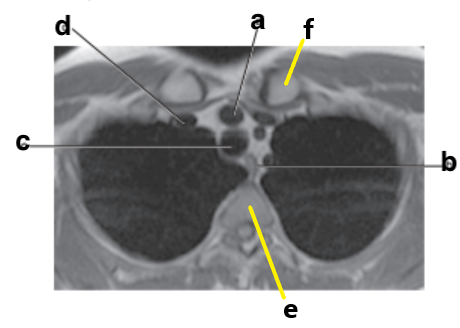

What is letter b ?

Esophagus

Left atrium

What is letter e ?

Vertebral body

What is letter c ?

Hemiazygos vein

Aortic Arch

Trachea

Thoracic vertebra